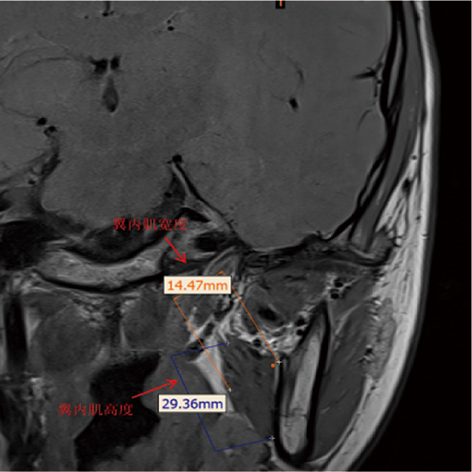

Ghadimi N, Mehralizadeh S, Rahimian E, et al. Correlation between the masticatory muscle dimensions and internal derangement of temporomandibular joints based on magnetic resonance imaging[J]. Iran J Radiol, 2023, 20(1): e131641.

Cezairli B, Halat İB, Balaban E. Evaluation of the correlation between articular disc displacement and the lateral pterygoid muscle using magnetic resonance imaging[J]. BMC Oral Health, 2025, 25(1): 1733.

Öçbe M, Medişoğlu MS. Magnetic resonance imaging of submental and masticatory muscle morphology and its relationship with temporomandibular joint structures[J]. Diagnostics, 2025, 15(12): 1535.